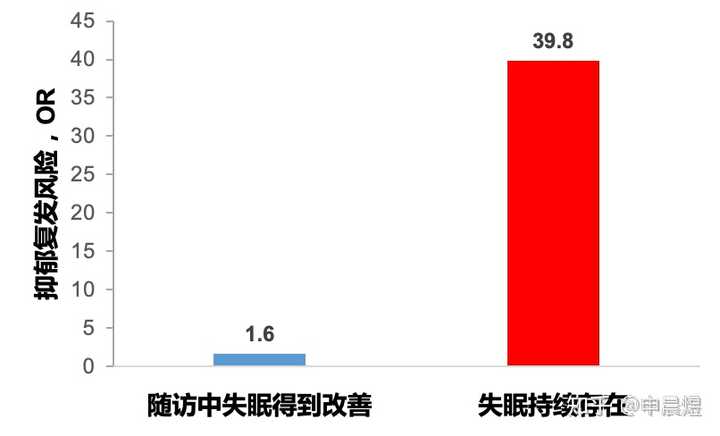

生物节律紊乱引发的睡眠障碍持续存在,可导致抑郁复发风险增高[4]。

与昼夜节律正常的同龄人相比,节律延迟的个体抑郁症状更严重,且更易出现轻度躁狂症状[5]。